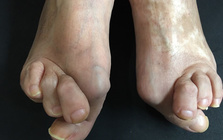

痛みを増し、変形症状、体を支える事が大変になり

歩行の困難、膝や腰などの痛みの発症に。

外反母趾の問題は痛みだけではありません。

その変形症状から多くの身体の不具合と

ほかの症状、病気を発症させてしまう方、

歳を重ねて健康、生活、行動の自由を奪われて

行く方が多いです。